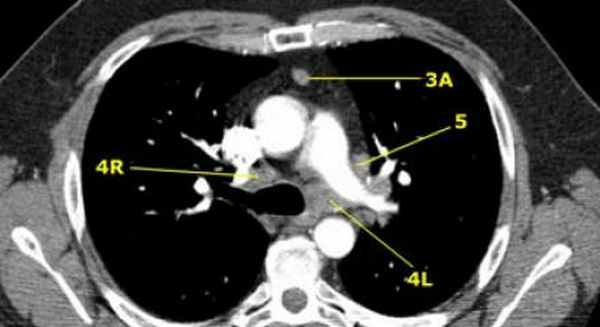

На изображении слева 3А узел в преваскулярном пространстве. Обратите внимание так же на ниже расположенные паратрахеальные узлы справа относящиеся к 4R группе.

4R. Правые нижние паратрахеальные лимфатические узлы

Верхняя граница: пересечение нижнего края левой плечеголовной вены с трахеей.

Нижняя граница: нижний края непарной вены.

4R узлы распространяются до левого края трахеи.

На изображении слева мы видим 4R паратрахеальные узлы. Кроме того здесь представлен узел кнаружи от дуги аорты, то есть 6 группы.

На левом изображении над уровнем легочного ствола представлены нижние паратрахеальные узлы слева и справа, так же здесь представлены узлы 3 и 5 групп.

Изображение слева выше уровня карины. Слева от трахеи 4L узлы. Обратите внимание что они расположены между легочным стволом и аортой, но не в аортопульмональном окне, потому что они лежат медиальнее артериальной связки. Лимфатические узлы латеральнее легочного ствола относятся к 5 группе.